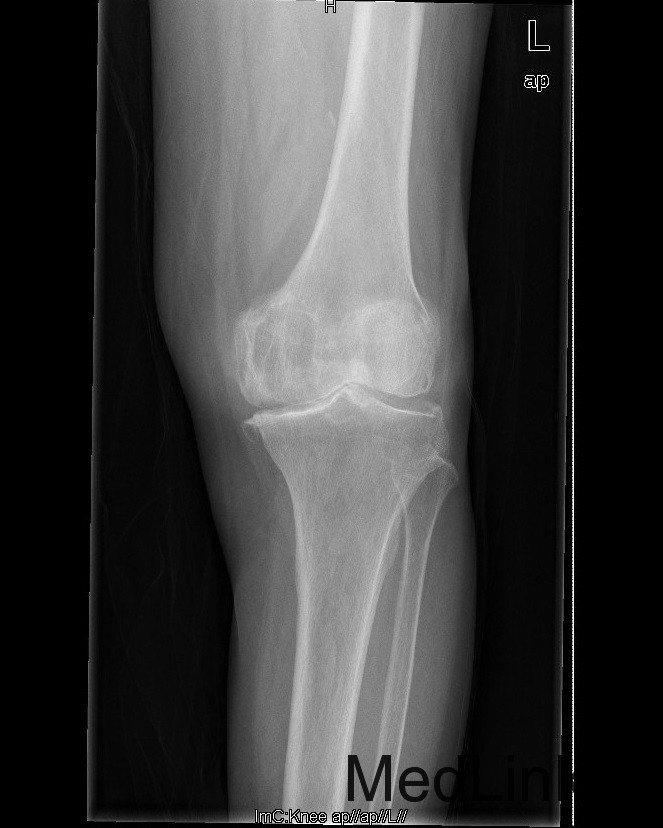

查体:查体:跛行步态,双膝关节屈曲内翻畸形,双膝内侧间隙压痛,双膝髌股关节间隙压痛,左膝伸-20°,屈110°内翻10°。右膝伸-20°,屈110°内翻10°,双膝屈伸活动时髌骨下摩擦感(+)。 辅助检查:双侧髌股关节内侧间室变窄,关节边缘骨赘增生,软骨下骨硬化。

诊断:1、双膝骨关节炎伴屈曲内翻畸形 左侧重2、高血压病(2级高危、) 治疗:在全麻下行左侧全膝关节置换术+软组织松解术,术后予以抗炎+抗凝+镇痛+补液+护胃治疗,并指导其功能锻炼。